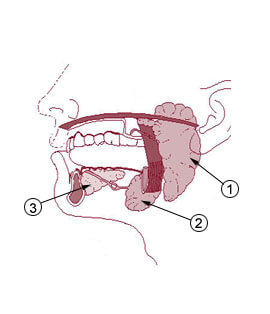

– Glándulas mucosas: aquellas que secretan mucinógenos (sustancia mucosa), que no son más que grandes proteínas glicosiladas que al hidratarse forman una sustancia lubricante y viscosa, de aspecto similar a un gel (la mucina), que es el principal componente del moco. Ejemplo de estas glándulas son las glándulas salivales menores de la lengua y el paladar y las células caliciformes.

– Glándulas serosas: secretan líquidos ricos en enzimas, un buen ejemplo de estas glándulas es el páncreas.

– Glándulas mixtas: como su nombre lo indica, estas glándulas tienen la capacidad de producir tanto sustancias tipo mucinogénos como secreciones serosas. Son glándulas mixtas las sublinguales y las submandibulares.

Así, estas glándulas participan directamente en el procesamiento de alimentos durante su tránsito por el tracto digestivo, comenzando por la cavidad bucal (con las glándulas salivales) y continuando en el estómago y el intestino delgado (glándulas intestinales y glándulas accesorias del sistema digestivo).

Las glándulas salivales también pueden inflamarse o recrecerse, lo que impide que ejerzan correctamente sus funciones y normalmente lleva al desarrollo de alguna enfermedad. Las paperas son un buen ejemplo de inflamación por infección viral de la glándula parótida en la cavidad bucal.